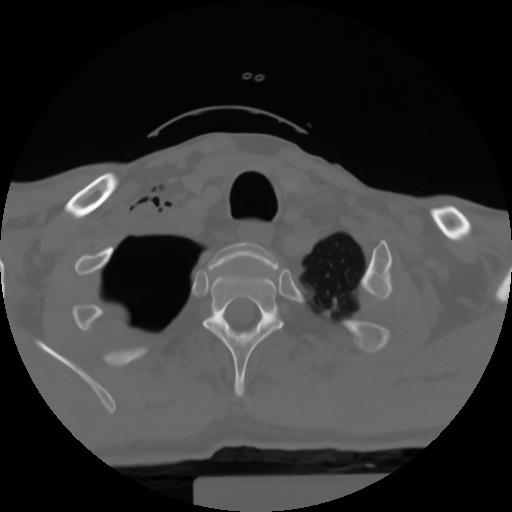

10 P.BLANDAS,,Axial,2.0,P.BLANDAS,,